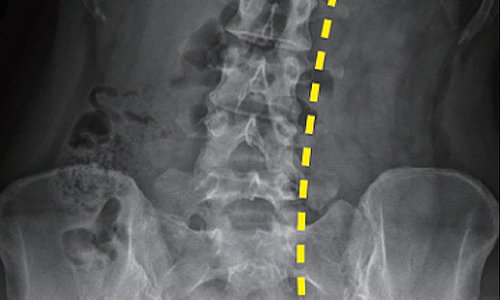

Before & After 척추측만증 교정 사례

• 30대 직장인

치료기간 3개월

BEFORE

AFTER